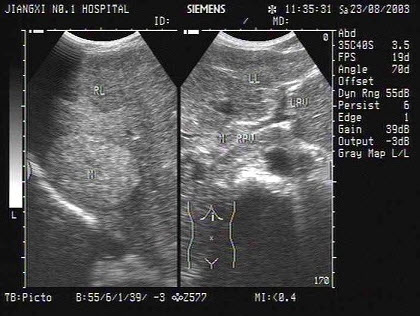

7、单项选择题

女,52岁,右上腹不适,CT示卵巢占位,结合超声声像图,诊断为()

A.肝囊肿

B.肝包虫病

C.转移性肝癌

D.肝脓肿

E.肝血管瘤

17、单项选择题

某患者肝脏声像图表现,最可能的诊断是()

A.肝转移癌

B.原发性肝癌并门脉癌栓

C.弥漫性肝癌

D.肝硬化并门脉海棉样变性

E.肝硬化并门脉血栓形成